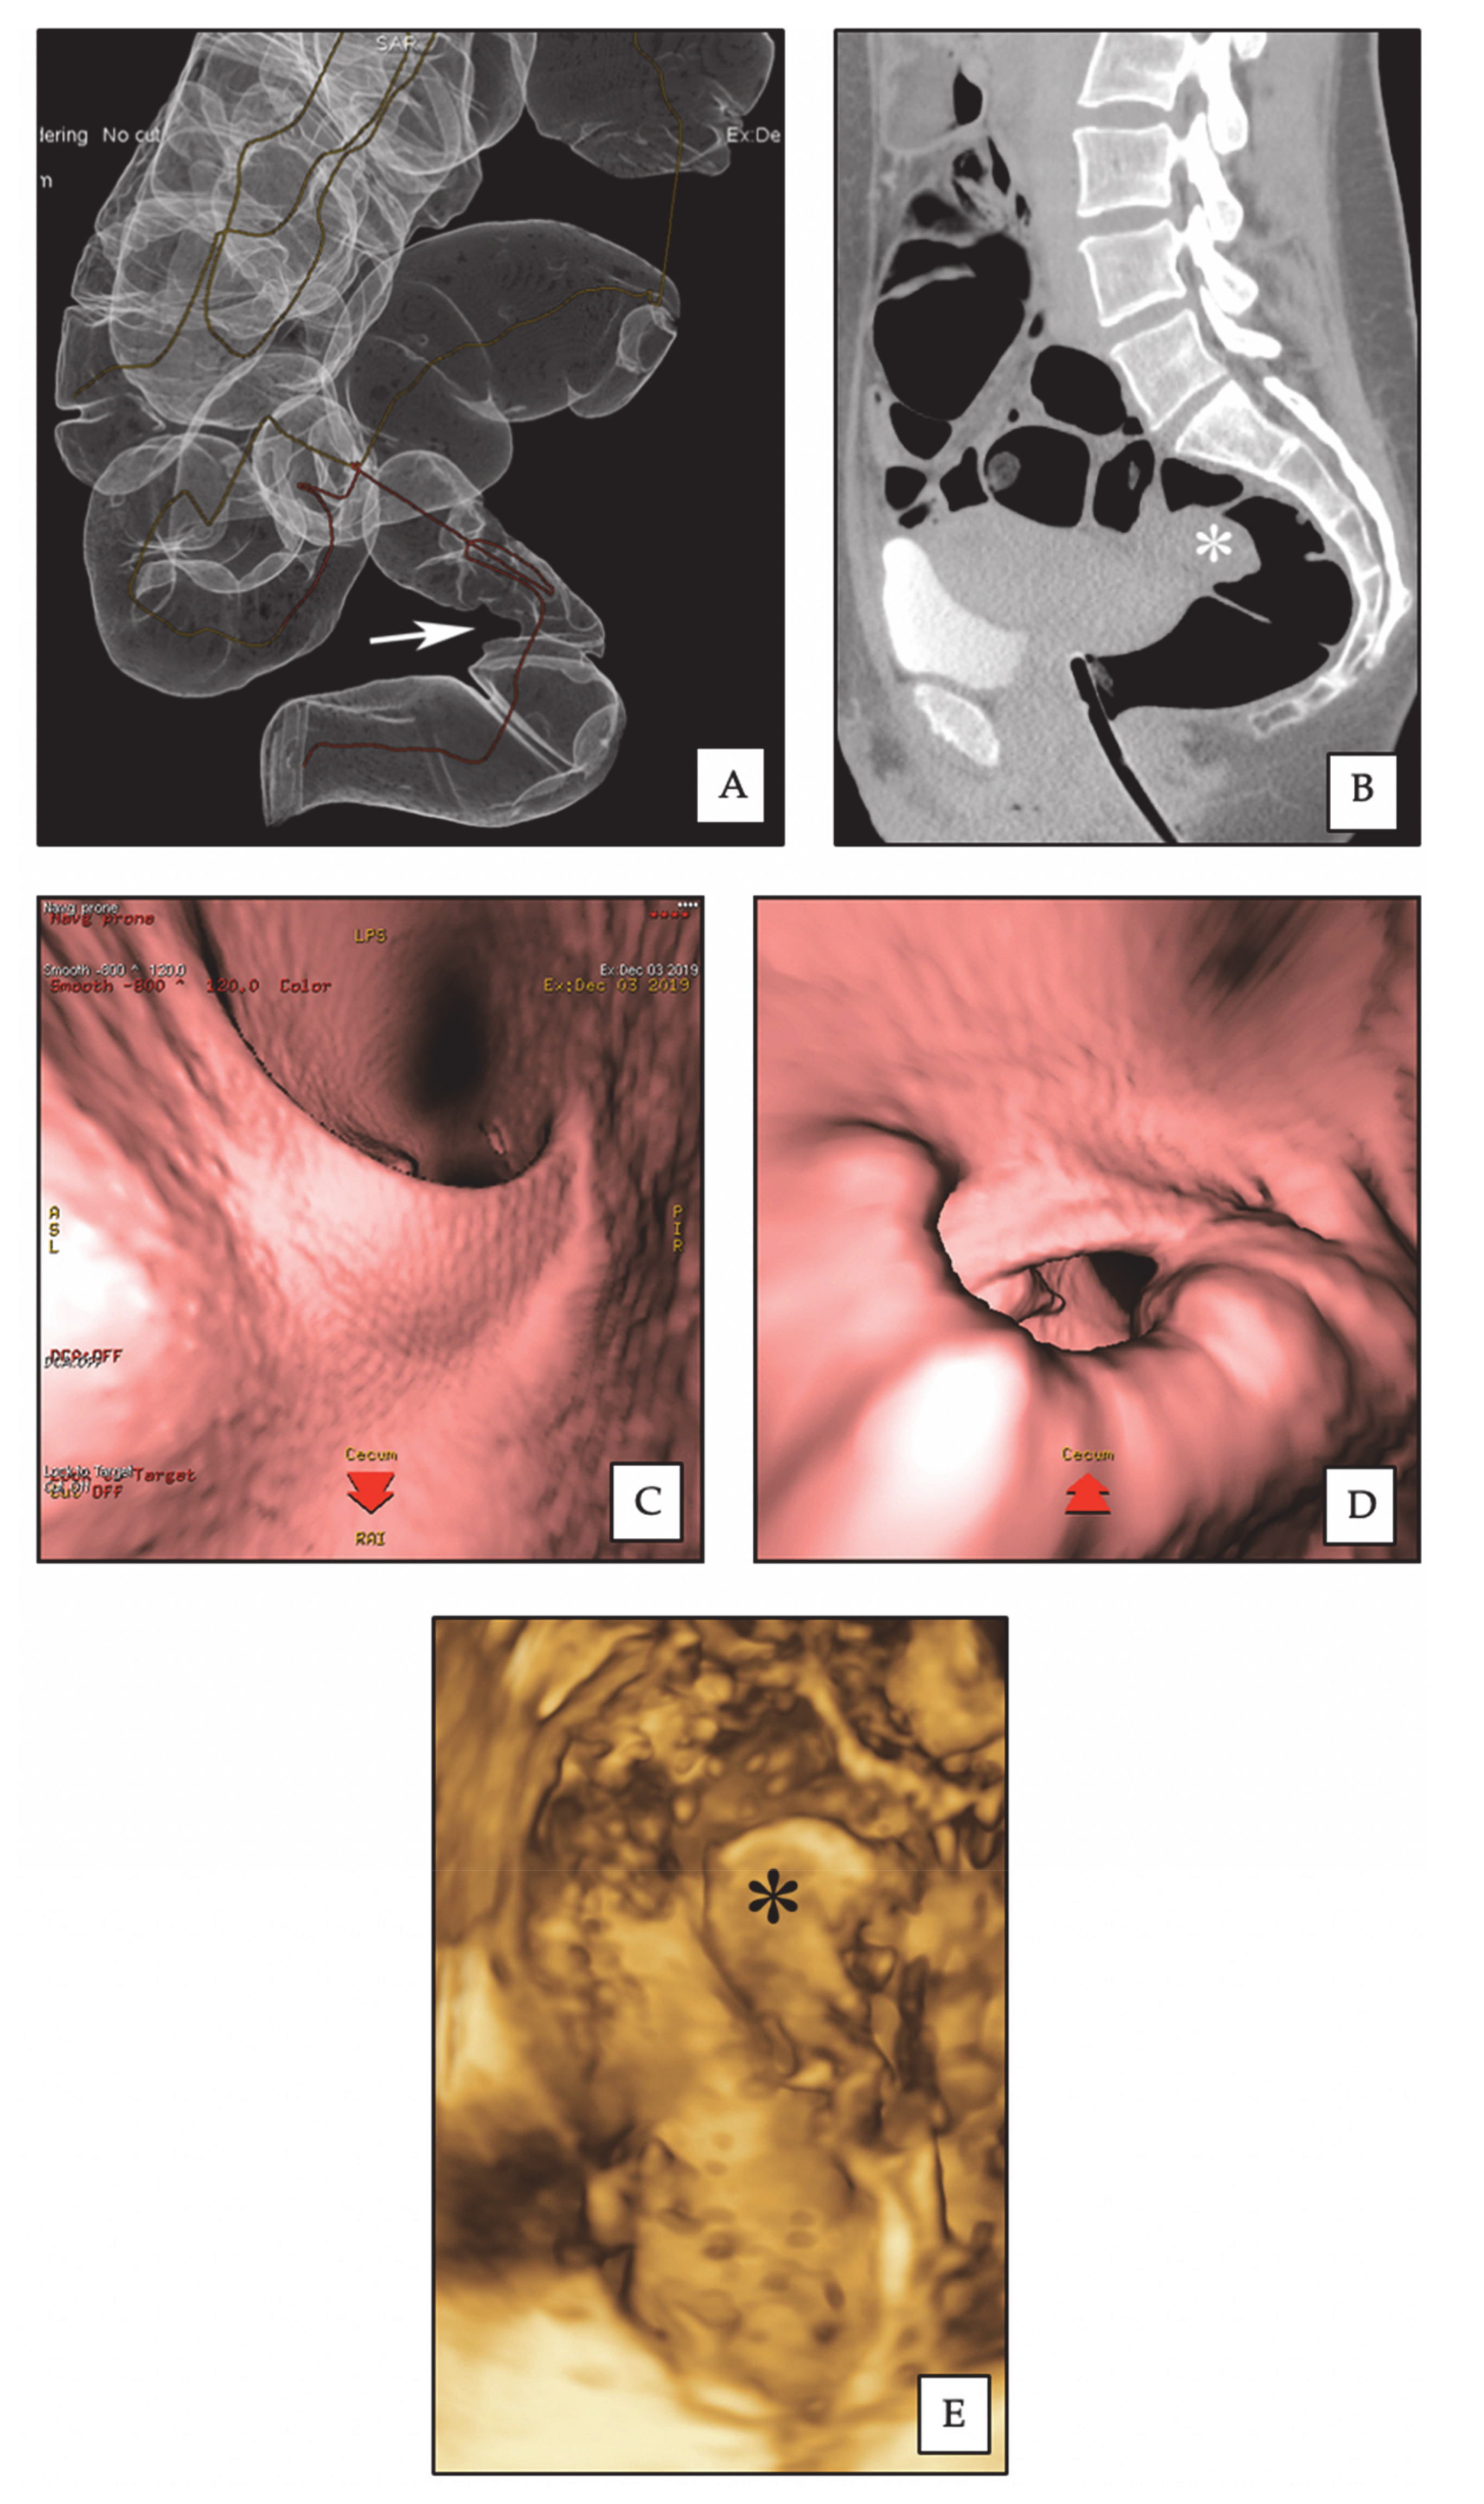

2.1. Three-Dimensional Rectal Water Contrast Transvaginal Sonography

2.2. Computed Colonography